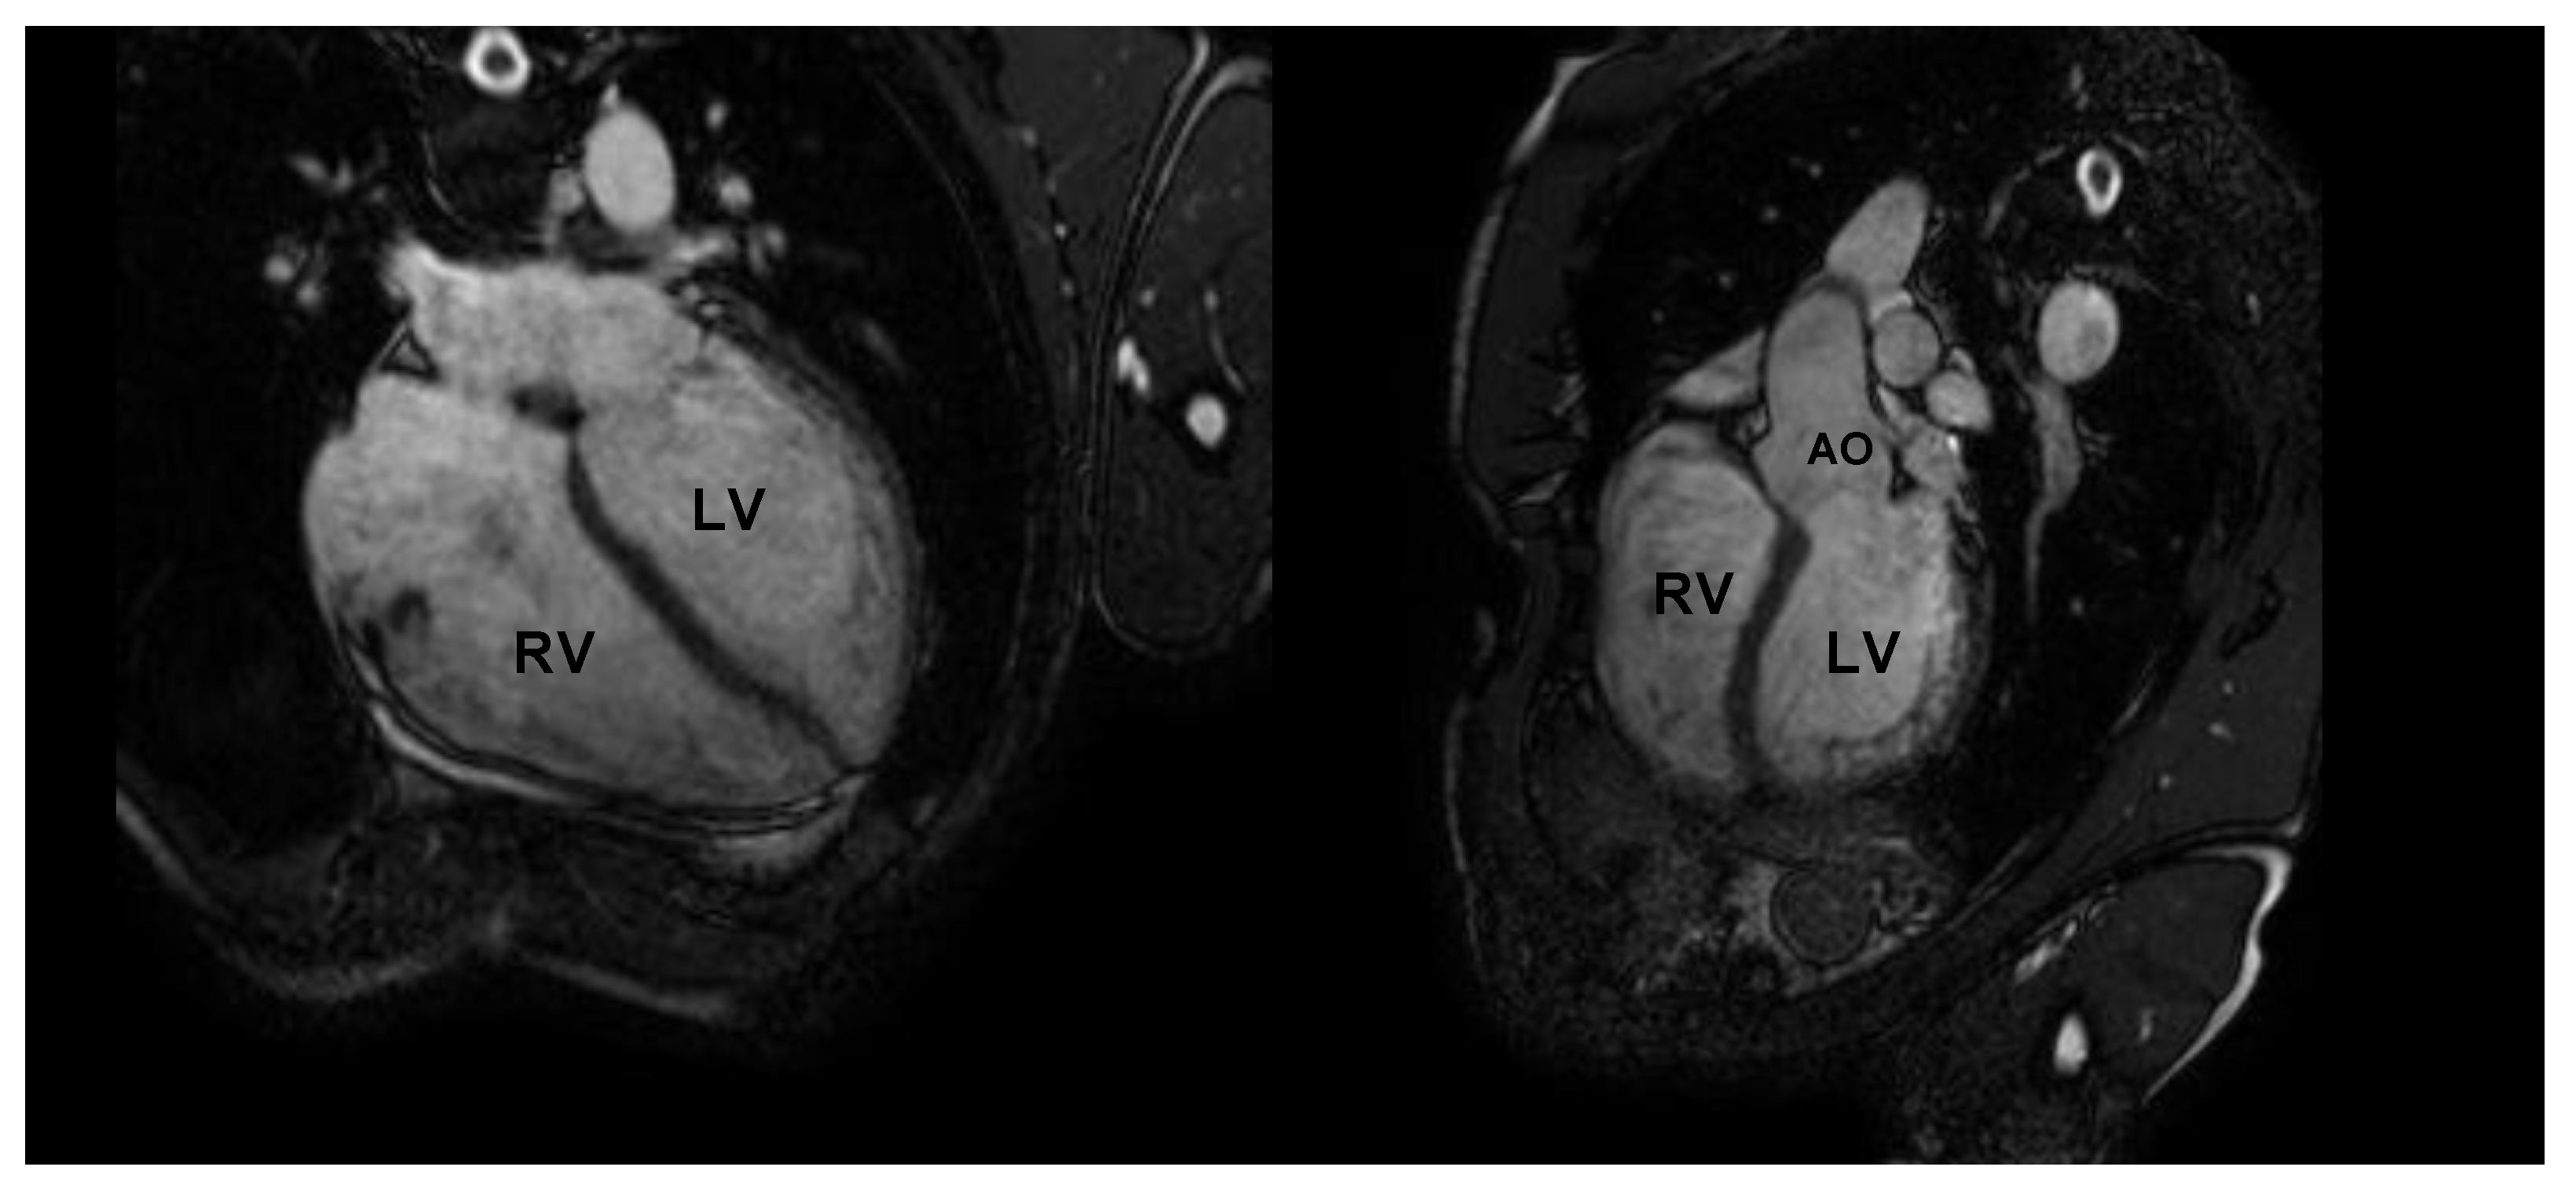

CMR is the gold standard for the definition of myocardial morphology, wall motion assessment, heart chambers size, and tissue characterization. It evaluates, with high accuracy and reproducibility, the heart chambers’ volume and mass, as well as global and regional contractile function [58,59,60]. It is the method of choice for the accurate evaluation of right ventricle morphology and function (Figure 4 and Figure 5).

Figure 4.

Cardiac magnetic resonance in an endurance athlete (long-distance swimmer). A symmetric dilatation of both right and left ventricular chambers is clearly depicted in 4-chamber (left panel) and 5-chamber (right panel) views. AO: aorta; LV: left ventricle; RV: right ventricle.